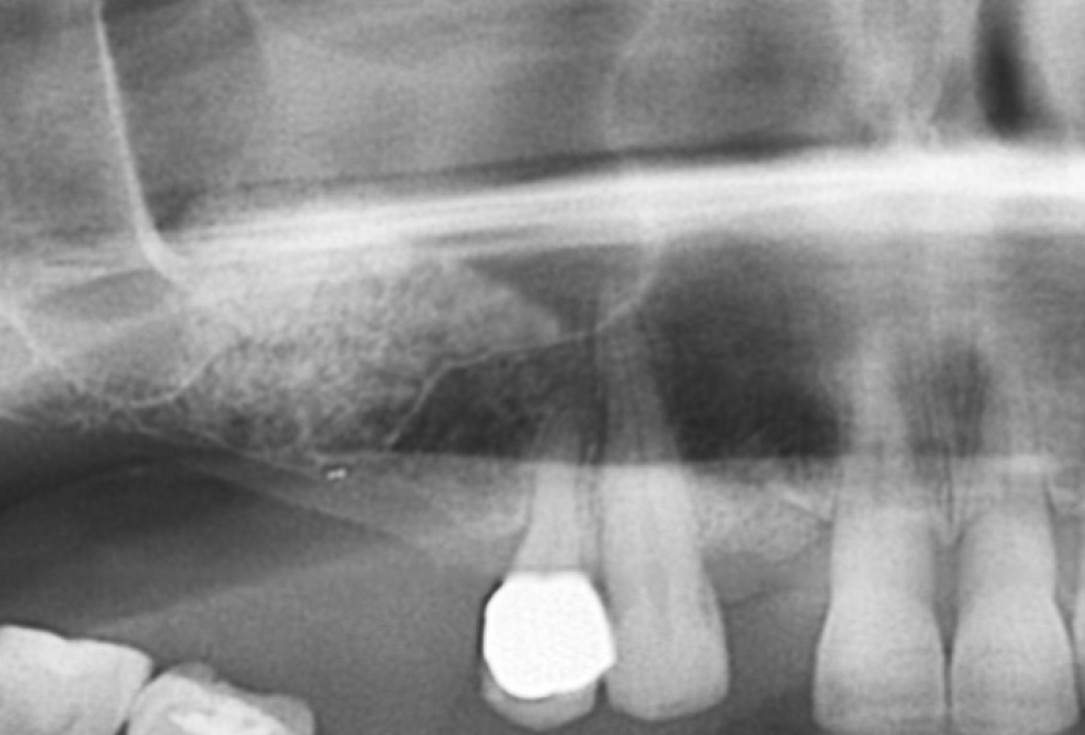

01/20 - Pre-operative x-rayGBR with maxresorb® & Jason® membrane - Prof. Dr. Dr. D. Rothamel

11/20 - Detail of OPG showing radiopacity of maxresorb®GBR with maxresorb® & Jason® membrane - Prof. Dr. Dr. D. Rothamel

Pre-operative x-ray